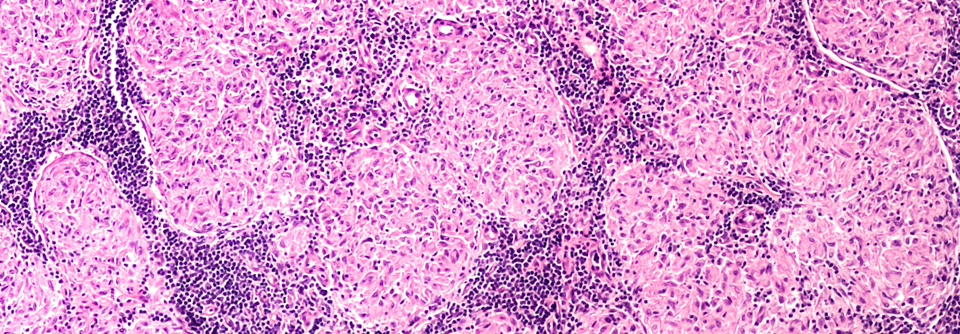

In der Biopsie vom Zahnfleisch fanden sich Makrophagen, Riesenzellen und wenige Lymphozyten. (Agenturfoto) In der Biopsie vom Zahnfleisch fanden sich Makrophagen, Riesenzellen und wenige Lymphozyten. (Agenturfoto) © iStock/Image Source

Diese entnahmen zunächst eine Gewebeprobe. Die zeigte eine Entzündung mit nicht-verkäsenden Granulomen, vielen Histiozyten, Riesenzellen und wenigen Lymphozyten. Die Ärzte um Privatdozentin Dr. Eva­ Valesky­ von der Klinik für Dermatologie, Venerologie und Allergologie der Universität Frankfurt vermuteten eine orofaziale Granulomatose im…